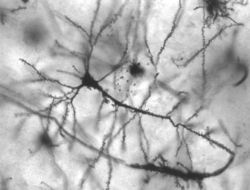

والعصبونات، مثل سائر الخلايا، محاطة بغشاء رقيق يكون الطبقة الخارجية، مع فارق أن غشاء العصبونات مُعَد بشكل خاص لنقل الدُفْعات العصبية. ويتكون العصبون من جسم خلوي وعدد من الألياف الأنبوبية الشكل. ويحمل أطول الألياف، الذي يسمى الجسم الخلوي، الدفعات العصبية من الجسم الخلوي إلى العَصْبُونات الأخرى. وتلتقط الألياف المتفرعة القصيرة، والتي تسمى التغصنات، الدُفْعات العصبية من محاوير العصبونات الأخرى إلى الجسم الخلوي. أما المشابك فهي المواضع التي تنتقل فيها الدُفعات العصبية بين الفروع العصبونية. وقد يكوِّن كل عصبون مشابك مع آلاف الخلايا العصبية الأخرى.

تغطي بعض المحاوير طبقة من مادة دهنية تسمى الميلين، وظيفتها عزل الألياف العصبية وتسريع انتقال الدُفْعات العصبية على سطحها. والميلين أبيض اللون، وتكوِّن المحاوير البيضاء المحزومة بإحكام داخل الميلين ما يعرف باسم المادة البيضاء. أما أجسام الخلايا العصبونية والمحاوير الخالية من الميلين، فهي تكوِّن المادة الرمادية للدماغ. وتتكون القشرة المخية من المادة الرمادية، بينما يتكون معظم الجزء الباقي من المخ من المادة البيضاء.

تحاط العصبونات بالخلايا الدبقية، وهي خلايا يعتقد أنها الإطار الداعم للعصبونات. وتؤدي الخلايا الدبقية أيضًا وظائف أخرى هامة. فبعضها، على سبيل المثال، يجعل الدماغ خاليًا من العصبونات المصابة أو المريضة؛ وذلك بابتلاعها وهضمها. وبعض الخلايا الدبقية تنتج أغطية الميلين التي تعزل بعض المحاوير. وتشير بعض الدراسات المعملية إلى أن الخلايا الدبقية، تنقل أيضًا، مثل العصبونات، بعض الدفعات العصبية.